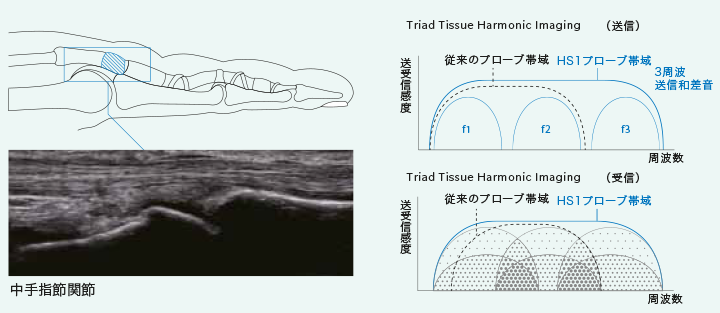

見えないものを視るために

超広帯域プローブの帯域を最大限活用した送受信技術を開発することにより、従来利用することが難しかった高次高調波を用いた超広帯域ハーモニックイメージングが可能となりました。複数の周波数成分を合成送信する方法(Tri ad- THI )により、プレミアムクラスに迫る分解能を超広帯域化で達成するだけでなく、高調波の多重生成機構(Tandem Harmonic Generation) の実現に成功しました。これにより従来THIの課題であった表層・浅部を含めた関心領域全域の高画質化を実現しています。